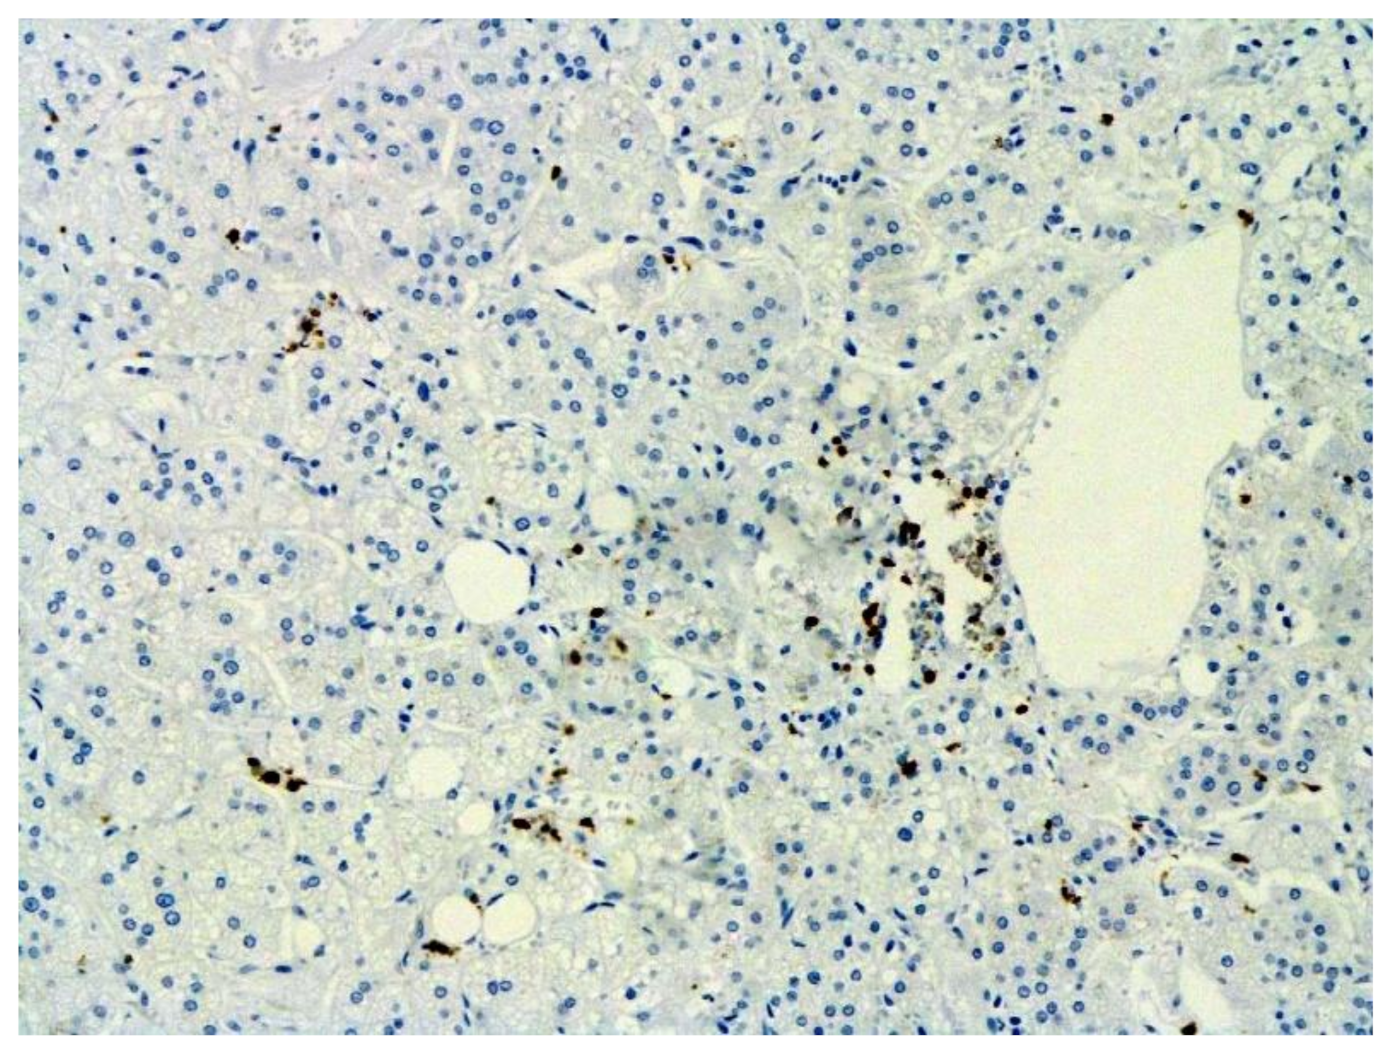

Figure 12.

CD68+ macrophages in lung. IHC ×200.

The dynamics of changes in ARDS associated with COVID-19 can only be judged by analogy with SARS and influenza A/H1N1pdm. In the late (productive) stage (after 7–8 days or more from the onset of the disease) of diffuse alveolar damage, macroscopically the lungs are enlarged, low-air, dense, fleshy, and can resemble the density of the liver, sometimes with diffuse whitish layers and areas of different sizes. Microscopically, siderophages, a relatively (in comparison with swine influenza) small number of hyaline membranes (Figure 9), fibrin, squamous metaplasia of the bronchial, and bronchiolar and alveolar epithelium can be detected in the lumens of the alveoli, respiratory and terminal bronchioles, the thickening of the interalveolar septa due to sclerosis, lymphoid (mostly CD3+ and CD 8+) (Figure 10 and Figure 11) and macrophage (Figure 12) infiltration, and the proliferation of type II alveolocytes. The nature of cytoproliferative changes of the epithelium in the trachea and bronchi remains unclear. In the final stage of the disease, sections of fibrous tissue may develop in all parts of the lungs (usually in the lower lobes) (Figure 13), which contributes to the development of chronic respiratory failure. It is notable that near the overgrowth of collagen fibers in the lungs, neoangiogenesis is also typical (Figure 14). The electron microscopic study revealed changed viral particles (Figure 15).